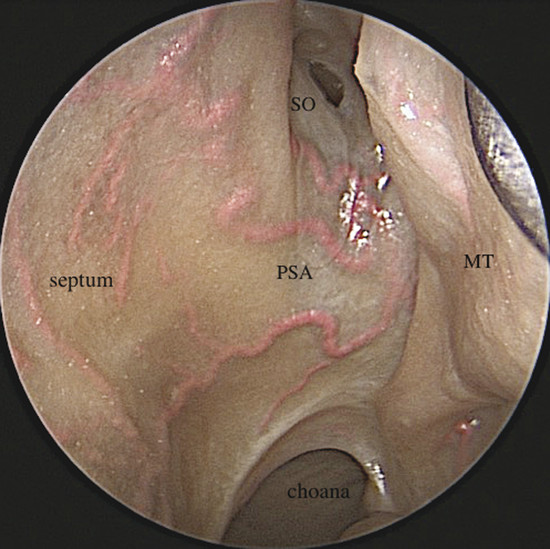

It is the terminal branch of the MA that emerges from the superomedial part of the PF and enters the nasal cavity through the sphenopalatine foramen. This foramen is usually located in the superior meatus, although it may also be found in the middle meatus or at the transition of both meatuses, according to its location above or below the ethmoidal crest. This anatomic landmark is an optimal bone reference to localize the sphenopalatine artery because it is just posterior to this crest (Fig. 3‑2).

It gives off two main branches, the posterior lateral nasal artery (PLNA) and the posterior septal artery (PSA), 1 , 2 which can be divided into one or two trunks medial to the ethmoidal crest, before or after crossing the sphenopalatine foramen. It is rarely possible to identify more than two trunks. 1 , 3 The PLNA supplies the region of the lateral nasal wall giving off branches to the inferior turbinate (inferior turbinate artery), middle turbinate (middle turbinate artery), mucosa of the fontanelle, and to the mucosa of the maxillary sinus 4 (Fig. 3‑3, Fig. 3‑4). In approximately 20% of cases this artery supplies the superior turbinate. 5 The inferior turbinate artery enters a bony canal and runs anteriorly along the turbinate. It usually gives off two terminal branches, within or adjacent to the bone, supplying the mucosa of the turbinate (Fig. 3‑5). The artery gives off several small vessels to the maxillary sinus and to the ethmoidal complex. The middle turbinate artery gives off several branches, some of which run along the medial surface of the turbinate whereas the other branches supply the lateral turbinate surface and anterior ethmoidal complex (see Fig. 3‑3).

The PSA crosses the anterior wall of the sphenoid sinus in a subperiosteal plane, between the choana and sphenoidal ostium. In most cases the artery bifurcates into the superior and inferior branches (Fig. 3‑6). In this area it supplies the superior turbinate (superior turbinate artery), sphenoid sinus, and posterior ethmoid complex. The superior turbinate artery can arise from the superior division of the PSA or directly from the trunk of the PSA. 6 The PSA branches on the nasal septum irrigating the inferior two-thirds. The distal extreme of the inferior branch of the PSA, the nasopalatine artery, vascularizes the inferior septal area and ends in the incisive canal where it anastomoses with the greater palatine artery (GPA). 1 , 2 Furthermore, the PSA presents anastomosis in the septal area with the ethmoidal arteries and with branches from the SLA (Fig. 3‑7).